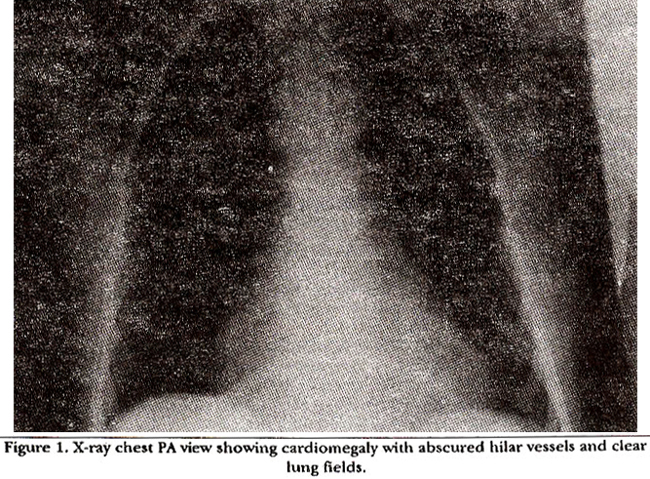

On admission her white cell count was 8,500/mm3, haemoglobin 11.5 G/dl; MCV 87; HCT 35; ESR 75, electrolytes Na 136, K 3.7 HCO3 24, Cl 97, Bun 3.8, creatinine 86mg. X-ray chest showed mild cardiomegaly, no pulmonary congestion (Figure 1).